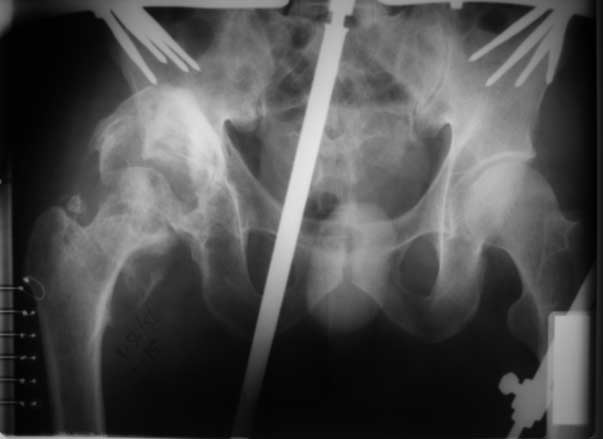

[Ortho] застарелый вывих бедра (продолжение темы http://weborto.net/forum/1226122957/index_html#1226722831)

репозиция 3 недели, артропластика Corail - Duraloc